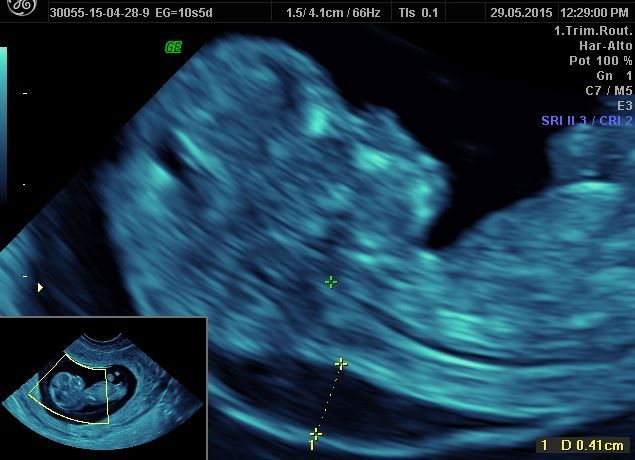

La prueba de translucencia nucal es un examen de detección que se hace durante el embarazo. Utiliza una ecografía para medir el grosor de la acumulación de líquido en la nuca del bebé en desarrollo. Si esta zona es más gruesa de lo normal, puede ser una señal temprana de síndrome de Down, trisomía 18 o problemas cardíacos.

La prueba se realiza entre las semanas 11 y 14 del embarazo. Puede hacerse como parte de la prueba de detección del primer trimestre o de la prueba de detección integrada.